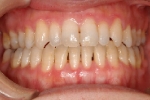

日本矯正歯科学会専門医課題症例(第7症例)

カテゴリー:開咬(overbiteがマイナスのもの)

| 初診時